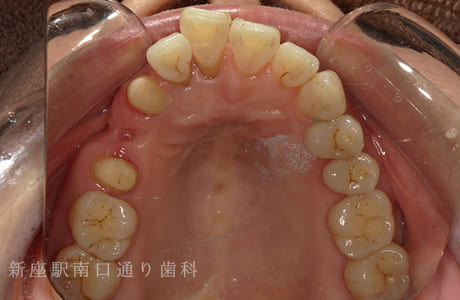

CASE.04

右上にフルジルコニアブリッジで

修復した症例

-

術前

術中

術後年

- 主訴

- 歯がないところを治したい

- 治療法

- 右上にフルジルコニアブリッジで修復

- 治療期間

- 1ヶ月半

- 費用

- ¥280,000(税込)

【リスク・副作用】

過度の咬合や衝撃で割れることがあります。治療直後は歯や歯茎に一時的な違和感や痛みが出ることがあります。